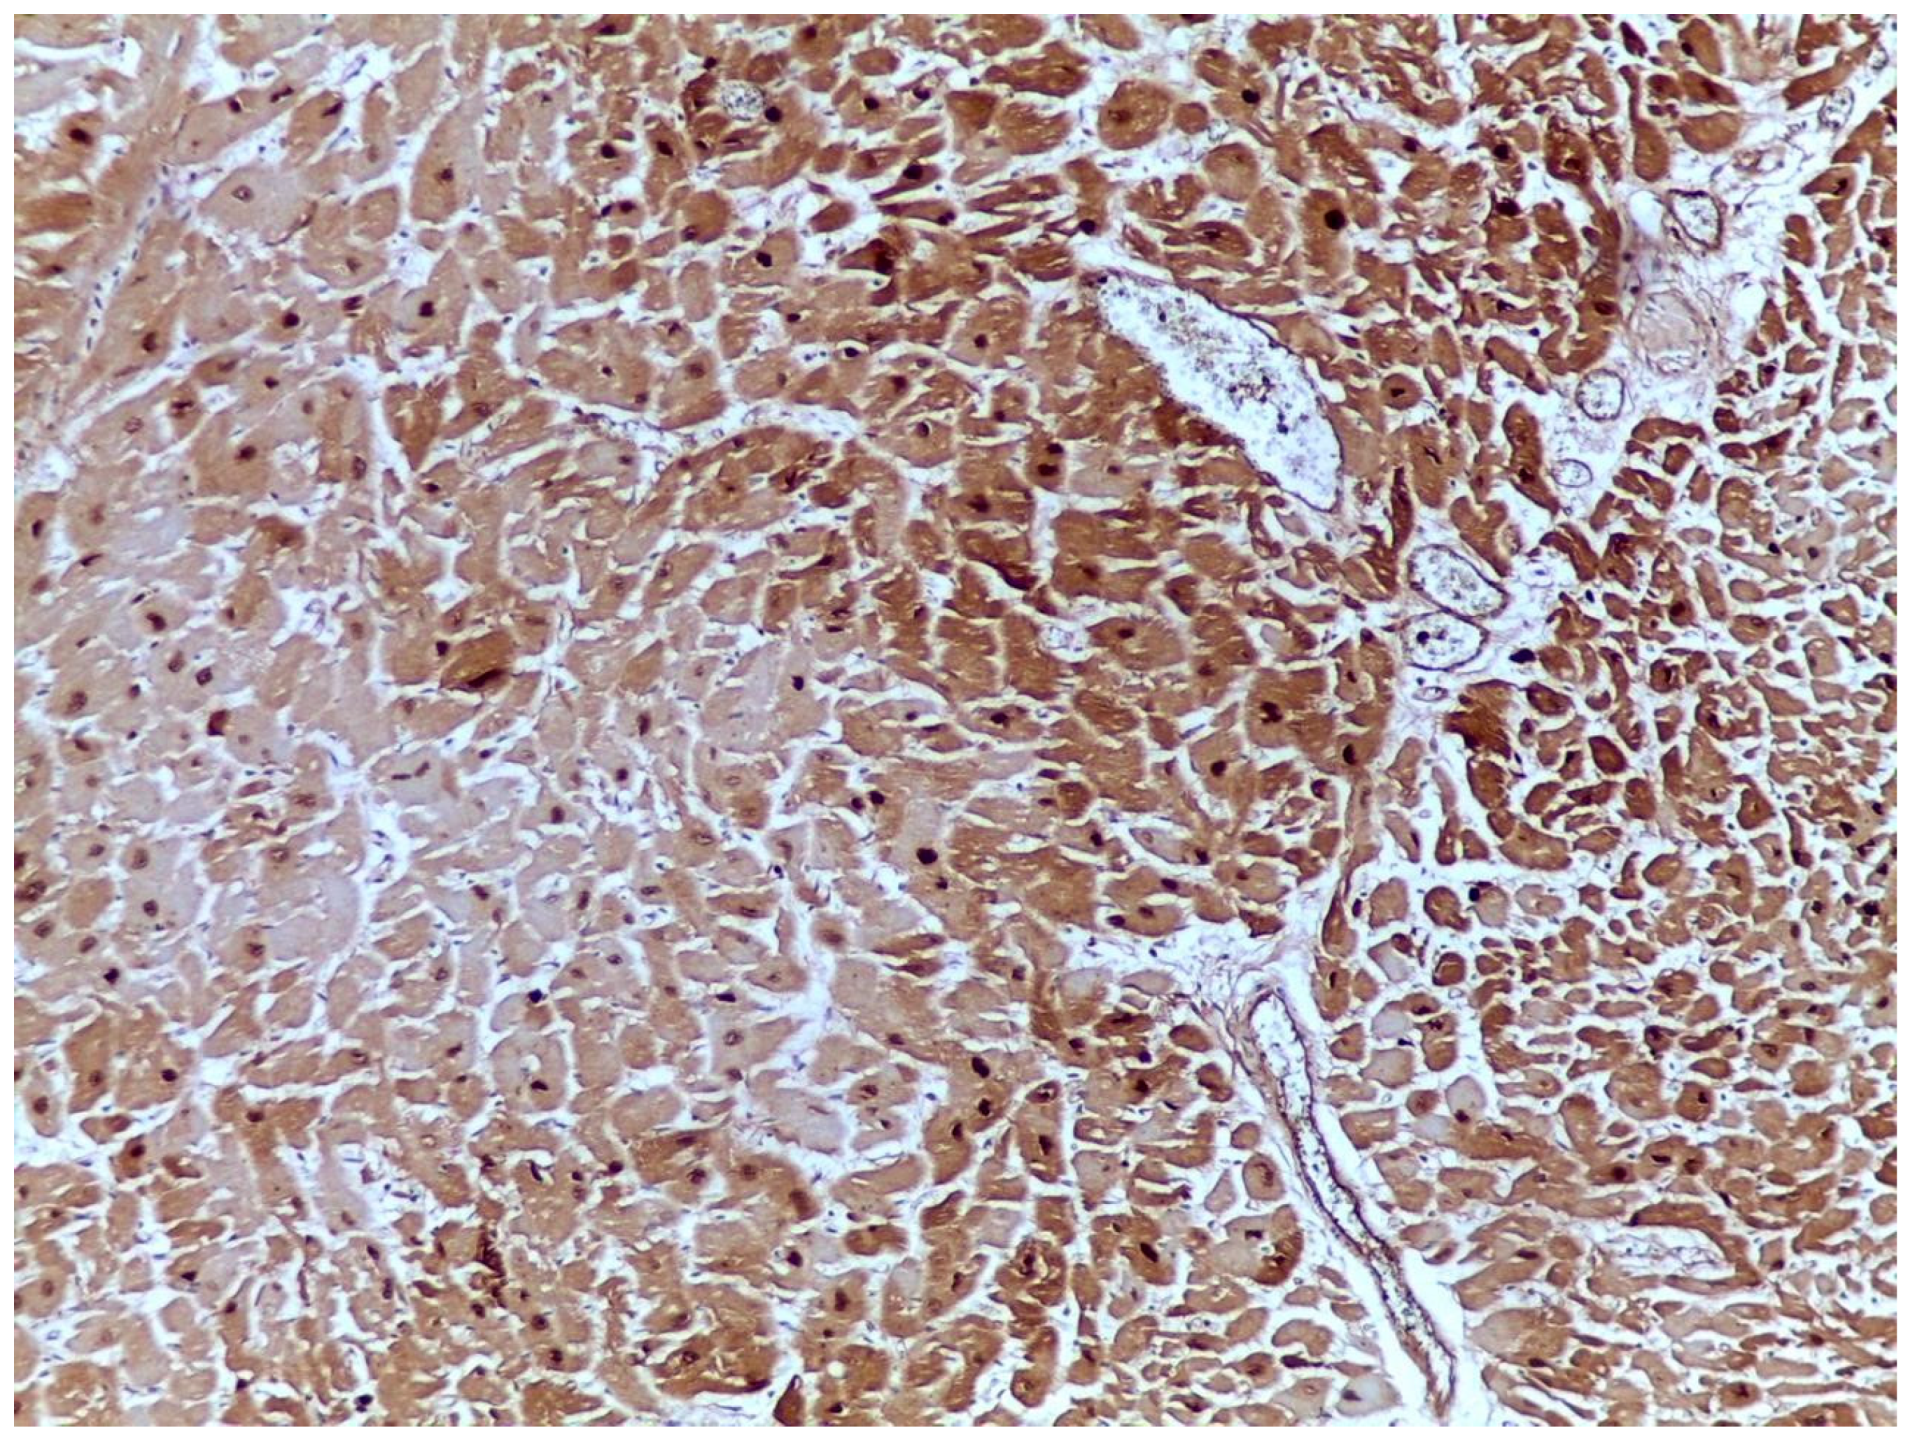

2.2. Myoglobin (MB)

2.7. Cardiac Troponins

2.8. H-FABP (Heart Fatty Acid Binding Protein)